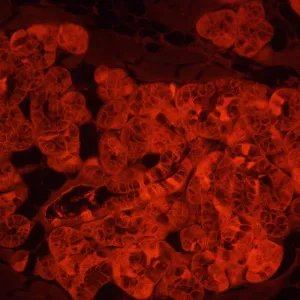

MAGUS Lum V500L – это инвертированный микроскоп для исследований люминесцентным методом в отраженном свете и методами светлого поля и фазового контраста в проходящем свете. Для люминесценции используются фильтры, оптимально подходящие для работы с флюорохромами DAPI, FITC и TRITC. Инвертированная конструкция позволяет изучать образцы в лабораторной посуде – чашках Петри, колбах и проч. Высота посуды может составлять 55 мм, а при отклоненном штативе – 165 мм. Оптика рассчитана на толщину дна посуды 1,2 мм. Микроскоп отлично подходит для исследовательской работы и рутинной лабораторной диагностики, может использоваться для обучения студентов вузов.

В качестве источника возбуждения люминесценции выступает светодиод мощностью 5 Вт и с ресурсом работы 50 000 часов без замены. Фильтров возбуждения три – для флюорохромов DAPI, FITC и TRITC. Светодиодное освещение более экономичное и простое в обслуживании, чем ртутное, поэтому рекомендуется для обучения в вузах. Светодиоды сохраняют постоянство цветовой температуры, быстро включаются и выключаются, не перегреваются при длительной работе.

- Фильтры возбуждения люминесценции для флюорохромов DAPI, FITC и TRITC

| Флуоресцентный модуль | фильтры (флюорохромы): DAPI, FITC, TRITC | |

| Фильтры возбуждения люминесценции: тип фильтра, длина волны возбуждения / дихроичное зеркало / длина волны запирания | DAPI, 365/35 нм / 400 нм / 450/65 нм; FITC, 475/40 нм / 500 нм / 535/45 нм; TRITC, 525/45 нм / 565 нм / 595/60 нм | |